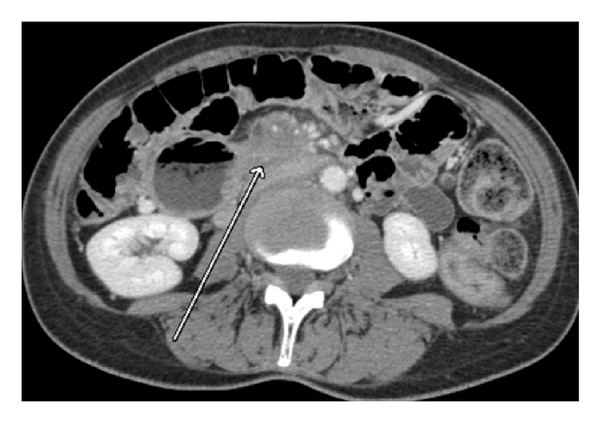

As Figures 1–5 demonstrate, the immediate postablation bed and zone are invariably larger than the original ablated tumor. We remain descriptive because the entire bed was extremely difficult to measure owing to the amorphous, irregular nature of the ablation. Moreover, the ablated tissue is not within an encapsulated organ; therefore, the ablation zone does not have defined borders as seen after, for instance, liver ablation. Four patients that showed continued stable disease are highlighted in Figures 1 through 4. An amorphous, hypoattenuating region with irregular shape persisted in subsequent CT scans in all patients with “stable disease.” Moreover, the ablation zone was typically smaller (due to decreased edema, hyperemia, and granulation tissue) than the immediate postablation bed in the following months and remained stable provided there was no recurrence. Imaging findings demonstrating recurrence are shown in Figure 5. Along with persistent irregular shape the ablation zone showed increased tumor bulk and extension as well as new mass effect (new narrowing of a blood vessel). Enhancement of the ablative bed was variable and often showed increased enhancement in the three-month and longer follow-up images. This was felt to be related to development of granulation tissue and fibrosis.

In our study, we found that the postablation bed is larger in volume than the initial mass. This is expected because it contains the tumor and the ablative margin. The postablation bed and zone appear irregular, amorphous, and hazy without margins or true boundaries. The ablation zone may decrease in size from the initial post-op bed to the initial surveillance study as the surrounding edema/fluid and inflammation resolve revealing the true ablation zone; however, as mentioned above, since there have been reports of an ongoing apoptotic process that persists up to 6–8 weeks after ablation, it will not be unusual to see some increase in volume in surveillance [19, 20]. Therefore, size is considered secondary in the CT evaluation for this reason and because the postablative bed/zone has poorly defined margins, making objective imaging assessment (size, attenuation) cumbersome. This may undoubtedly affect the accuracy and reproducibility of the measurement. Nonetheless, any increase in volume after stabilization of the postablation zone is considered worrisome for recurrence (Figure 5).

Other clues that may suggest recurrence are any new encasement or narrowing of adjacent vessels or any subjective extension of soft tissue outside the boundaries of the previously established baseline ablation zone. However, in patients that have undergone prior radiation therapy or undergo post-IRE radiation therapy, persistent isolated narrowing (without other worrisome findings) is not always recurrence and must be followed with serial imaging, clinical evaluation, and CA19-9 serum tumor markers. Vessels within and adjacent to the ablation bed may show narrowing immediately after the procedure, but this should resolve or at least remain stable in subsequent studies. Often, if narrowing of a vessel is seen with the index tumor it will often persist after ablation. For equivocal cases, PET/CT may play a role in differentiating postablative changes from recurrence [25].